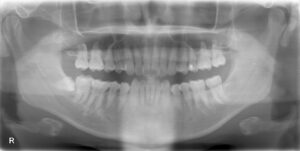

共に、画面向かって左下一番奥の親知らずの抜歯です。

2人とも歯茎の下に完全に埋まっておりました。